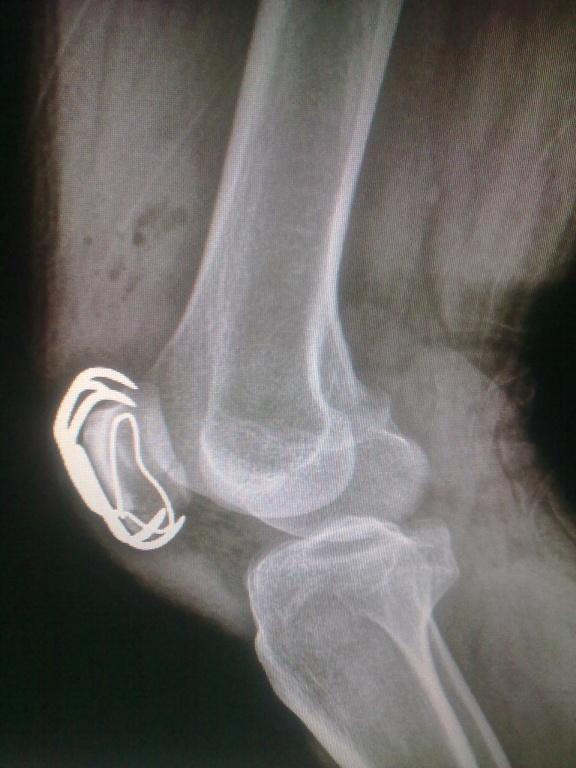

做的第一例髌骨骨折髌骨爪内固定。请大家看看!

患者男性.43岁,因骑自行车致右下肢受伤.***就诊,查体示:右膝关节肿胀明显.不能主动伸膝,皮下淤青,浮髌征(+).末梢感觉血运好!是个髌骨下极骨折!(术前片拍反了)前天手术完,今天发上来给老师们看看,有什么可指导的地方,谢谢!

做的漂亮,关节面很平。

手术做得不错,钢丝是不是有点多余,再一个材质不同要考虑电解问题

有点画蛇添足的了,用髌骨爪就不要用钢丝捆了,这样做在活动膝关节的时候钢丝容易折断。手术做得不错。